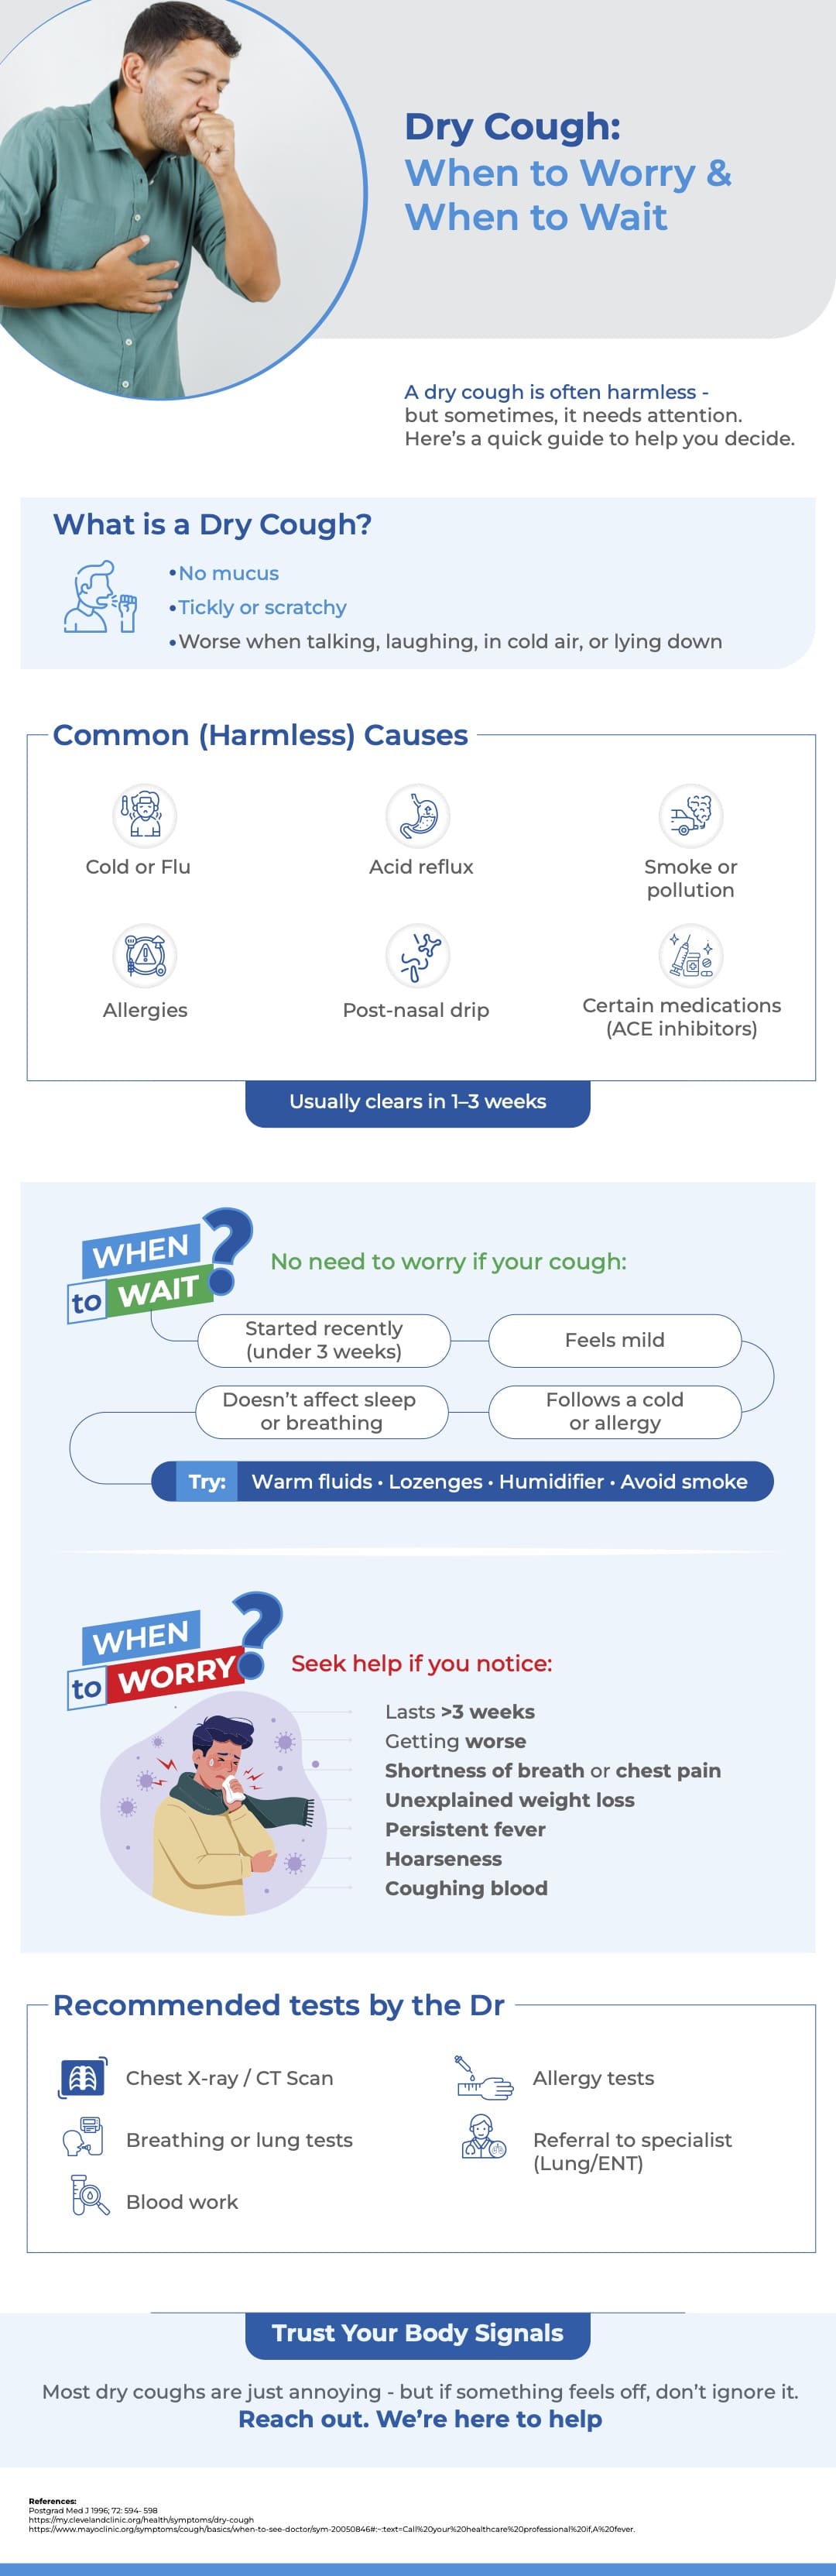

Dry Cough: When to Worry and When to Wait